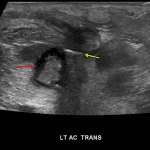

Indication: Soft tissue infection, rule out abscess

- Skin thickening and increased echogenicity of the subcutaneous fat in the area of concern in the left antecubital fossa

- Within this area is a collection measuring 1.8 x 1.5 x 1.1 cm with central echogenicity and no convincing internal vascularity

- Linear echogenic structure along the superficial margin of this collection with associated posterior acoustic shadowing

- This collection appears to be located within or immediately overlying the muscle, with the superficial margin approximately 1.5 cm deep to the skin surface

- Soft tissue abscess

- Cellulitis

- Foreign body

Skin thickening and increased echogenicity of the subcutaneous fat in the area of concern in the left antecubital fossa, compatible with cellulitis. Within this area is a collection measuring 1.8 x 1.5 x 1.1 cm with central echogenicity but no internal blood flow, concerning for an abscess. This collection is located 1.5 cm to the skin surface and may be within or immediately overlying the muscle.

Linear echogenic structure along the superficial margin of this collection with associated posterior acoustic shadowing, which may represent a linear array of gas or a retained foreign body.